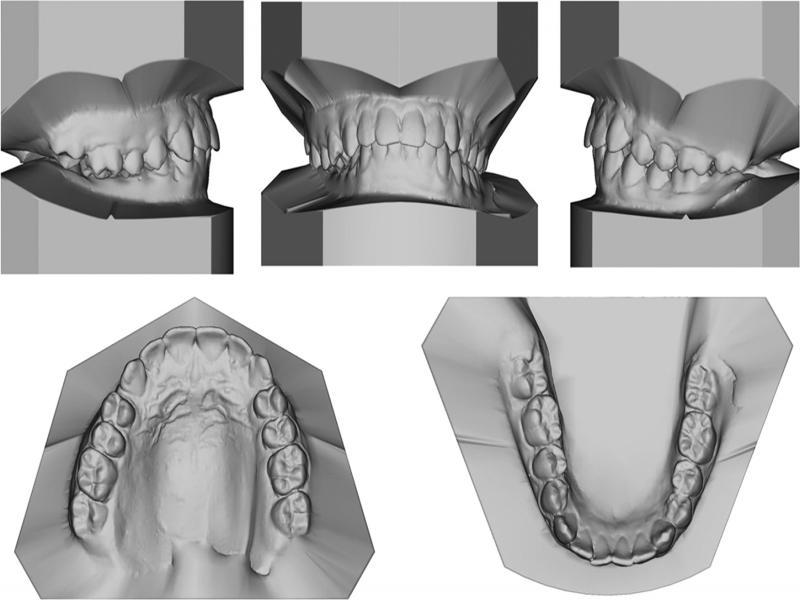

Figure 1.